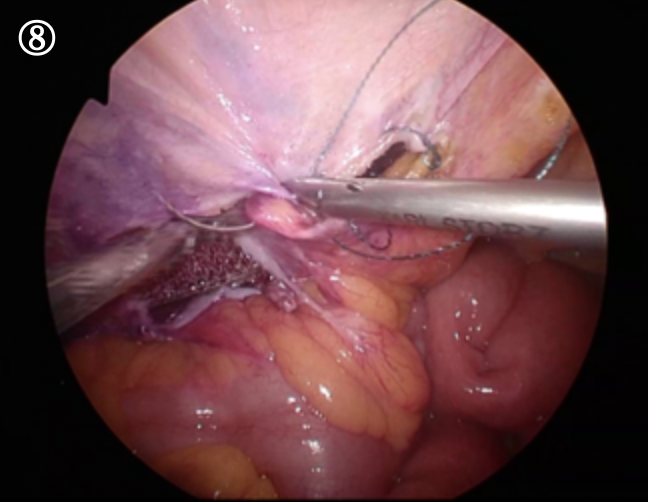

このヘルニア門に沿って腹膜という薄い膜を切っていきます。

全周に切り離した状態です。

最終的に広く腹膜をおなかの筋肉からはがしていきます

この腹膜をはがしたスペースに人口の布(メッシュ)を入れ広げ、溶けるスクリューねじで固定していきます

血管や神経を避けてねじを打ち込みメッシュを広げた状態です